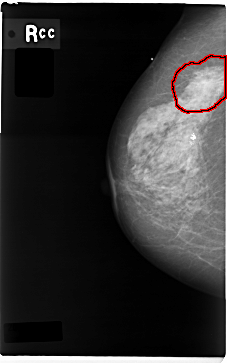

C_0004_1.RIGHT_CC

FILE: C_0004_1.RIGHT_CC.OVERLAY

TOTAL_ABNORMALITIES 1

ABNORMALITY 1

LESION_TYPE MASS SHAPE IRREGULAR MARGINS SPICULATED

ASSESSMENT 5

SUBTLETY 5

PATHOLOGY MALIGNANT

TOTAL_OUTLINES 1

BOUNDARY